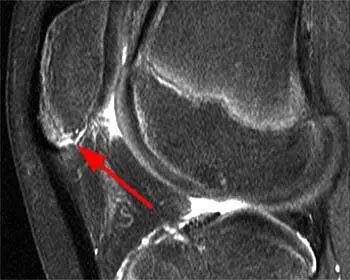

图4 一名患有膝前部疼痛的11岁男孩,患有Sinding-Larsen-Johansson 病。(a)髌骨下极有轻微碎裂。(b)矢状位T2加权脂肪抑制(T2-W FS)图像证实了碎裂情况,并显示出轻度骨髓水肿和髌腱增厚。https://radiologykey.com/the-lower-extremity-congenital-and-developmental-conditions/。

图6-2:在相应的脂肪抑制T2加权矢状位图像上,髌骨下极内的骨髓水肿(箭头所示)清晰可见,这与Sinding-Larsen-Johansson 病相符。https://radsource.us/developmental-variants/